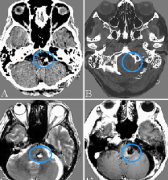

右側(cè)三叉神經(jīng)根底部的動靜脈瘤樣結(jié)構(gòu)(AVM)破裂而導(dǎo)致蛛網(wǎng)膜下腔出血。與以前的病例相比,他的病史中沒有三叉神經(jīng)痛或感覺喪失的證據(jù)。右椎動脈造影顯示小腦上動脈雙倍供血于...